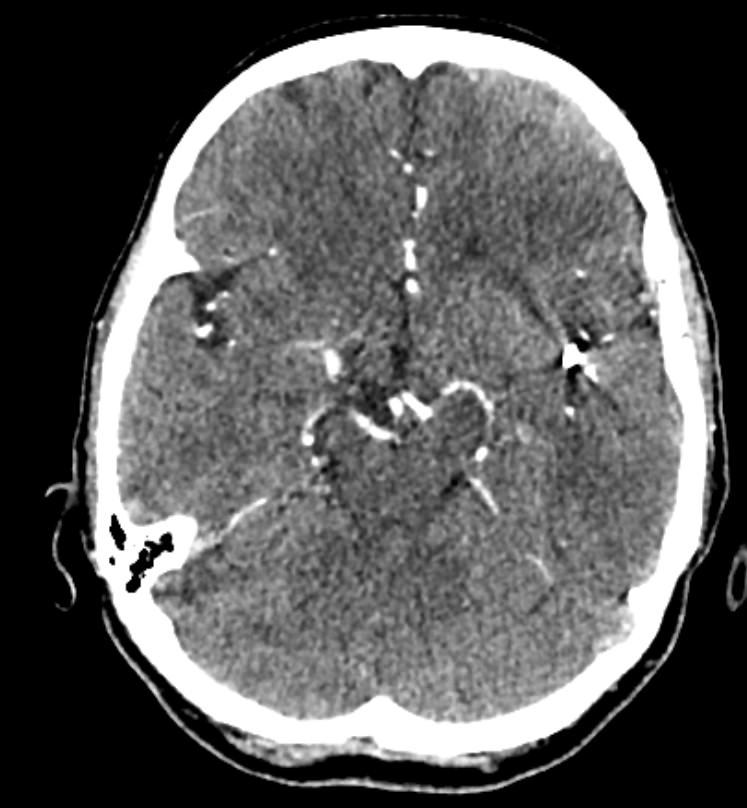

Мультиспиральная компьютерная томография сосудов головного мозга (КТ-ангиография) относится к лучевым методам исследования и применяется для оценки состояния сосудистого русла головного мозга. КТ-ангиография основана на применении рентгеновского излучения, при этом обязательно проводится контрастирование сосудов головного мозга.

Процедура заключается в том, что трубка томографа вращается вокруг анатомической зоны исследования и с помощью рентгеновских лучей делает послойные снимки, которые затем реконструируются в трехмерные изображения сосудистой системы в мельчайших подробностях. При этом по сравнению с классической ангиографией компьютерная томография не требует вмешательства в организм пациента и проводится в амбулаторных условиях.

Высокая диагностическая информативность КТ-ангиографии в сочетании с быстротой и неинвазивностью делают эту процедуру безопасной и эффективной методикой обследования сосудов головного мозга у пациентов с неврологической симптоматикой. Но особенную ценность КТ сосудов головного мозга имеет в плане скринингового обследования. Это позволяет выявлять аневризмы (расширение стенки артерии), патологическую извитость, аномалии развитии (артериовенозные мальформации), сужения просвета сосудов за счет атеросклеротических бляшек или экстравазальной, например вертеброгенной, компрессии и другие серьезные заболевания, которые долгое время могут протекать бессимптомно.

КТ-ангиография головного мозга в нашей клинике проводится на современных мультиспиральных компьютерных томографах последнего поколения TOSHIBA AQUILION. Благодаря инновационным компьютерным программам получаются детализированные снимки высокого качества и 3D-модели сосудистой системы головного мозга. При этом аппараты обеспечивают пониженный уровень лучевой нагрузки на организм пациента.

Для лучшей визуализации сосудов в обязательном порядке в вену пациента вводится йодсодержащий контрастный препарат. Контрастное вещество поглощает рентгеновские лучи, поэтому даже мелкие сосуды становятся хорошо видны на фоне окружающих тканей.